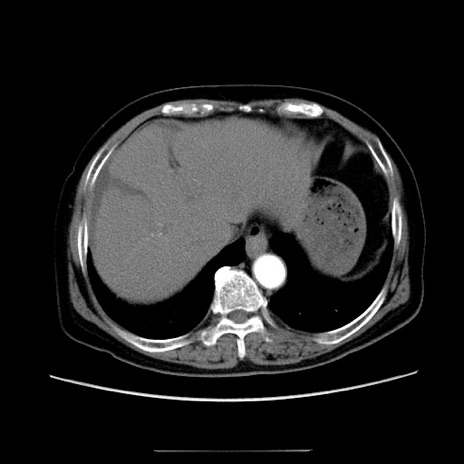

症例5(横断像)

【症例】70歳代女性

【主訴】お腹が張る

【現病歴】1週間くらい前から腹部膨満の自覚あり。昨日夜から増悪したため、本日救急外来受診。

【身体所見】意識清明、BT 36.5℃、BP 165/106mmHg、HR 80bpm、SpO2 98%、腹部:膨満、軟、自発痛・圧痛なし、触診にて不快感あり、腸蠕動音:減弱

【データ】WBC 12600、CRP 1.04